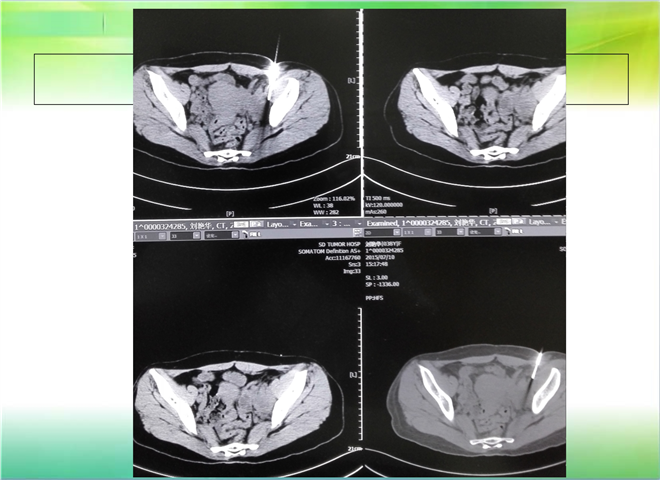

CT引导下穿刺活检术